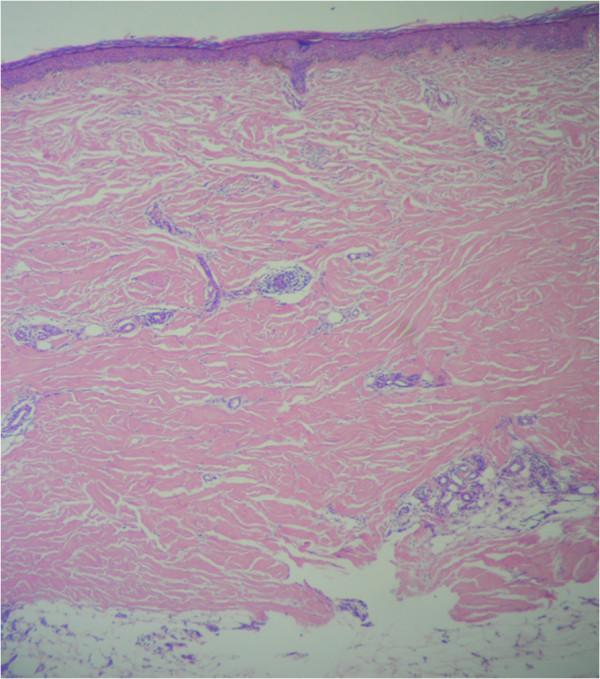

The localized scleroderma (LS) known as morphea, presents a variety of clinical manifestations that can include systemic involvement. Current classification schemes divide morphea into categories based solely on cutaneous morphology, without reference to systemic disease or autoimmune phenomena. This classification is likely incomplete. Autoimmune phenomena such as vitiligo and Hashimoto thyroiditis associated with LS have been reported in some cases suggesting an autoimmune basis. To our knowledge this is the first case of a morphea forming part of a multiple autoimmune syndrome (MAS) and presenting simultaneously with autoimmune thrombocytopenic purpura and central nervous system vasculitis.

We report an uncommon case of a white 53 year old female patient with LS as part of a multiple autoimmune syndrome associated with pneumonitis, autoimmune thrombocytopenic purpura and central nervous system vasculitis presenting a favorable response with thrombopoietin receptor agonists, pulses of methylprednisolone and cyclophosphamide.